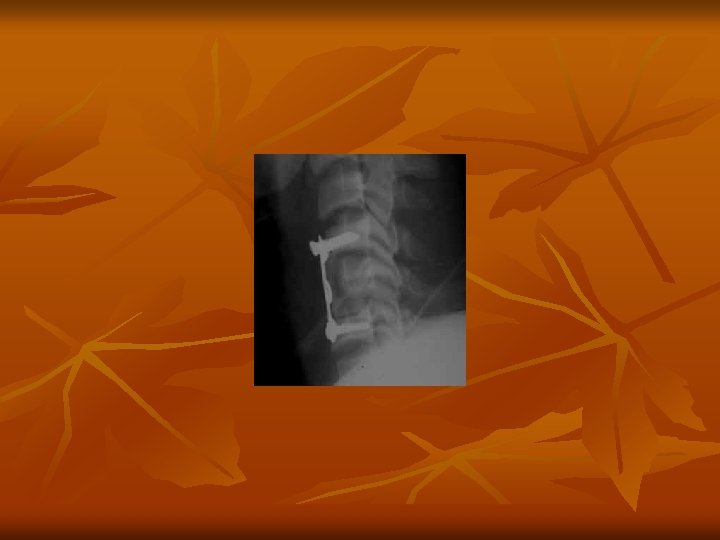

CERVICAL CORD INJURY n n Minimum 2 -view cervical spine x-rays done in every patient and it is first investigation after entering emergency Department ------ preceded by clinical assessment and starting MPS. ONLY Lateral view is most informative in all Cases. If required dynamic x-ray Lateral view. Followed by MRI of cervical spine.

CERVICAL CORD INJURY Group 3 - C 5 -6, 6 -7 disectomy with C 6 corpectonsy with bone graft 60/M Fall on ground 6 days Incomplete 34/F Fall on Ground 10. 5 Hrs. Incomplete Conservative 55/M Fall from Chair 27 Hrs. Incomplete Conservative UL 3/5 LL 4/5

CERVICAL CORD INJURY Results analysis – Group 3 and 4 n All had trivial trauma like fall from bicycle of tripped on floor. n All had INCOMPLETE cord injury except one. n All had pre-existing Spondylotic changes. n Only 2 of these seven had # dislocation. n None has cord contusion.